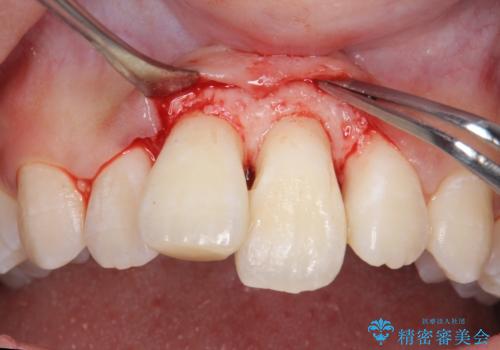

前歯の角度や歯ぐきのラインに差が大きかったため、やむなく神経をとり、歯ぐきの手術を行い出来るだけ歯ぐきのラインを整えるようにしました。

手術をしなければ左上1番の歯ぐきのラインは左上2番よりも下にきてしまい、長さの短い歯になってしまうところでした。

手術をしなければ左上1番の歯頚ラインは左上2番よりも短い位置になっていたため、歯自体の長さが不自然なほど短くなってしまったと思います。